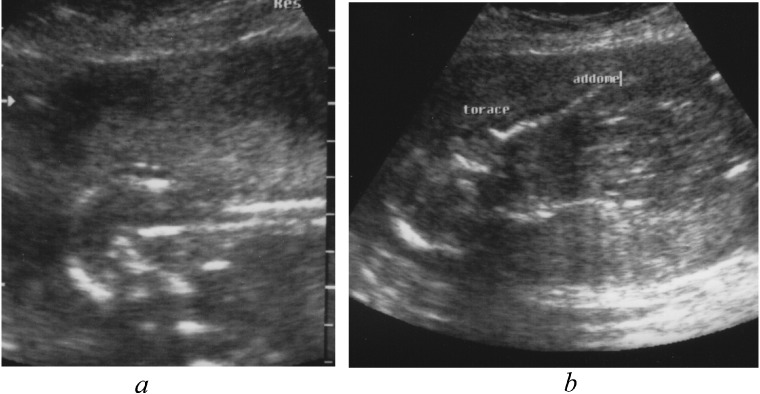

Fig. 1.

Prenatal ultrasound showing occipital encephalocele (a) and enlarged kidneys (b).